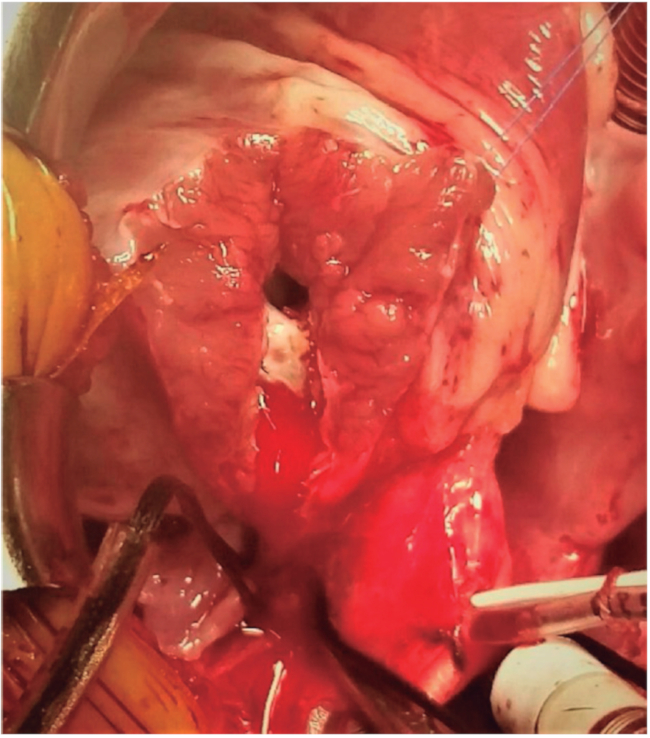

Los stents utilizados fueron coronarios o periféricos con un diámetro que varió entre 4,0 y 6,0 mm. Dos pacientes recibieron dos stents telescopados para cubrir la totalidad del TSVD. No se registraron complicaciones durante la intervención. El tiempo de internación fue de 7 días (1-13) y el tiempo de seguimiento fue de 106,8 días (4-292). No hubo mortalidad a los 30 días ni hasta la cirugía correctiva, realizada con éxito en los dos primeros pacientes, quienes fueron intervenidos a los 7 y 10 meses de vida, respectivamente, con técnica de parche transanular y extracción subtotal del stent (Figura 3). Se registró un evento de extrasístole ventricular frecuente que requirió tratamiento con drogas posintervención. Además, en dos pacientes ingresados al procedimiento en crisis de cianosis con hipoxemia grave en ARM desarrollaron convulsiones que se trataron con la administración de fenobarbital y levetiracetam, respectivamente.

Imagen durante la corrección quirúrgica completa mostrando tracto de salida de ventrículo derecho con stent parcialmente extraído.